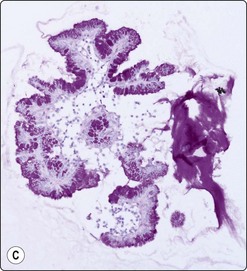

image image image

Fig. 11.7 Solid-pseudopapillary neoplasm

(A) Vessel associated pseudopapillary fragment (Pap, LP); (B) Pseudopapillary fragment. Note small tumor cells and irregular outer border with detached tumor cells (MGG, IP); (C) Cell block section showing positive staining for progesterone receptors (PR, IP).

Solid-psedopapillary neoplasm (Figs 11.7 and 11.8)

Criteria for diagnosis

Extremely cellular,

Branching papillary fronds comprising central slender fibrovascular cores of myxoid stroma lined by one or more layers of neoplastic cell which are exfoliating with dispersal,

Acinar arrangements with central metachromatic material (pseudorosettes),

Small epithelioid cells with bland round to oval nuclei, occasional longitudinal nuclear grooves, finely granular chromatin and inconspicuous nucleoli,

Balls or globules of PAS-positive myxoid stroma and psammoma bodies,

Background of foamy macrophages, multinucleated cells and necrosis.

This relatively uncommon low malignant potential pancreatic neoplasm, with its many pseudonyms, occurs almost exclusively in young women under the age of 20 years.64 They usually behave in a benign manner but 10–15% of cases show spread or metastases. Still considered to be of uncertain histogenesis, this tumor is thought to be hormonally dependent. Occurring anywhere along the length of the pancreas, the mass is usually sizeable at presentation, averaging 8 cm. Grossly, as well as on imaging studies, it is characterized by good circumscription, multiloculation and solid and cystic areas. The histopathologic features, which are specific and diagnostic, are mirrored exactly by the cytologic pattern in FNB smears. Initial tumor growth is solid, but degeneration results in clefts, eventually enlarging to cysts, between vascularized cell fragments, which then appear ‘pseudopapillary’.

Fifty isolated case reports or limited series attesting to the ability of FNB to confidently identify this unusual but widely reported neoplasm were summarized in 2002 by Pettinato and colleagues in a definitive paper.64 Richly cellular smears demonstrate characteristic pseudopapillae and pseudorosettes, composed of small tumor cells adherent to delicate metachromatic fibrovascular stalks. Recognition of this stromal component is essential in distinguishing this tumor of relatively good prognosis from similar small-celled pancreatic neoplasms. The outline of both the pseudopapillae and the pseudorosettes appears irregular, due to exuberant exfoliation of single cells into the smear background. These vascular-based aggregates vary from large grape-like branching structures to single capillaries with leaf-like single-cell linings (Fig. 11.7). These cells are small, round to oval, plasmacytoid or cuboidal and extremely monotonous. Cytoplasm is variably preserved, vesicular to faintly granular, containing characteristic eosinophilic, hyaline intracytoplasmic globules, which are PAS positive. Nuclei are round and even, with grooves but no major irregularities or significant pleomorphism. Chromatin is described as finely granular, without clumping or clearing. Small nucleoli may be appreciated and are occasionally multiple. In the background, foam cells, multinucleated giant cells, debris and laminated psammoma bodies reflect the cystic and papillary nature of the parent tumor. Mucus is absent. Diagnostic accuracy of EUS-FNA has been reported as 75% in a series of 28 cases.65